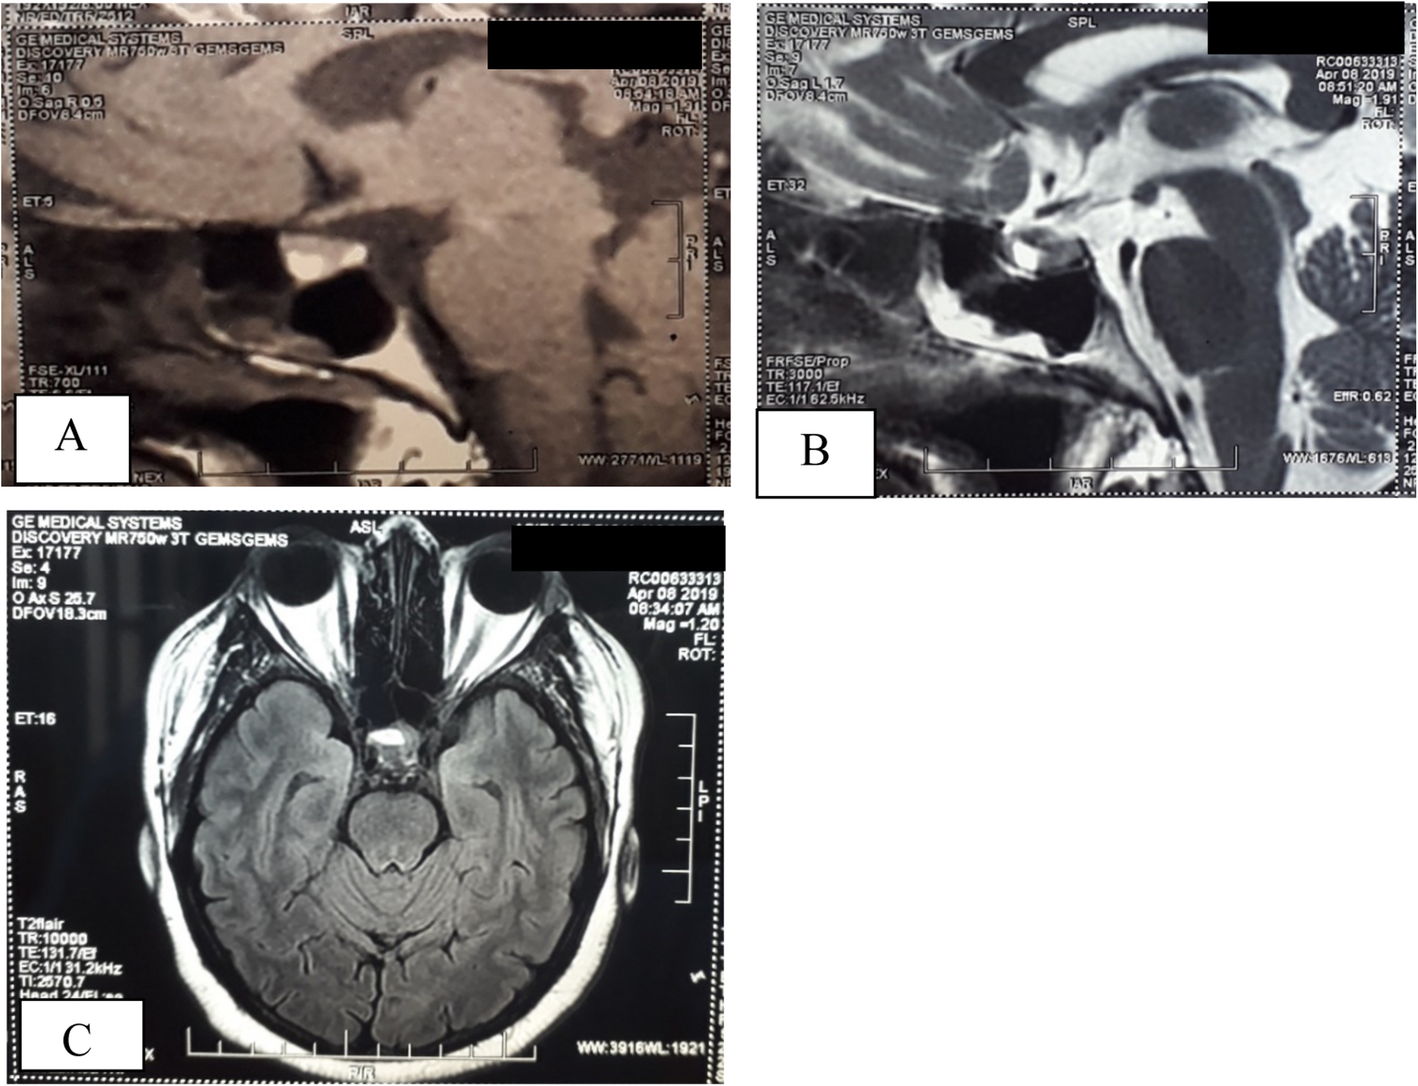

Fig. 2From: A challenging case of Cushing’s disease complicated with multiple thrombotic phenomena following trans-sphenoidal surgery; a case reportMRI showing high signal lesion of 10x8x9 mm suggestive of pituitary microadenoma. a T1 contrast sagittal. b T2 sagittal. c FLAIR axialBack to article page